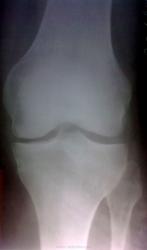

Публикации: 805

суставная щель неравномерно сужена, преимущественно во внутреннем отделе, суставные поверхности немного уплотнены, заострен медиальный лимбус большой берцовой кости. Я бы поставила 1 ст., на 2-ю не тянет))))))))))))))

По представленным рентгенограммам четко высказаться о Р-признаках артроза трудно. Если память мне не изменяет, минимальная высота суставной щели в коленке может минимум до 3 мм, но это нельзя считать формальной причиной для заключения об артрозе. В данном случае можно высказаться об артрозе (1 ст), но это будет субъективно, только при ссылке на клинические данные (если они имеются).

а разве 1 стадию мы видим на снимках? артрозные изменения есть, больше в медиальном отделе сустава, ввиде субхондрального склероза,  сужения суставной щели ( по-сравнению с наружным отделом), легкие краевые заострения. боли при это могут иметь место. надо знать как человек нагружает ногу.

OPEXOB , а как вы объясните разную высоту суставной щели и субхондральный склероз суставной поверхности внутреннего мыщелка б.берцовой кости?

Гонартроз справа 1 ст.

Но обязательно прокомментирую представленное описание. В современной России по-прежнему действует классификация атрозов, которую называют "по Н.С.Косинской". Краткое изложение: 1ст. - суставная щель то ли сужена, то ли нет; 2ст. - суставная щель несомненно сужена; 3ст. - суставной щели почти не видно. Т.о. данное описание противоречит заключению: рентгенолог пишет "суставная щель несколько сужена" (т.е. неочевидно), следовательно - 1 ст.,  а в заключение выставляет вторую. Что ту сказать? "ТщательнЕЕ надо"(с)Улыбаюсь

На мой взгляд, в настоящее время, об артрозе говорить не приходится. Некоторое неравномерное сужение суставной щели (без процесса остеофитообразования и субхондрального склероза) может быть объяснено и несостоятельностью внутрисуставных компонентов суствава - связки, мениски и пр., а возможно и вальгусной деформацией стопы, вальгусной установкой пятки, да можно много объяснений найти.

"Высота" или скорее ширина ? Она не изменена. Должна быть в двое выше ширины кортикального слоя.

Субхондрального склероза нет.

На данном снимке нет признаков деформирующего (обезображивающего) остеоартроза.

Фактическая высота (ширина) суставной щели разнится практически в 2 раза...так что - проблем НЕТ?

Извините, Игорь Иванович, но все таки - 2-я ст...а если бы снимок был еще и более структурным то мы все "нарыли" бы еще ряд существенных проблем...и они бы подтвердили 2-ю ст.

Так что нам не остается другого, как все таки признать тут вторую ст., ибо здесь НЕТ сомнений (то ли есть, то ли нет сужение) в сужении суставной щели.

Я уже не говорю о том, что в центре проекции внутреннего мениска имеется небезосновательное подозрение на наличие "вакуум-феномена"...присмотритесь пожалуйста...